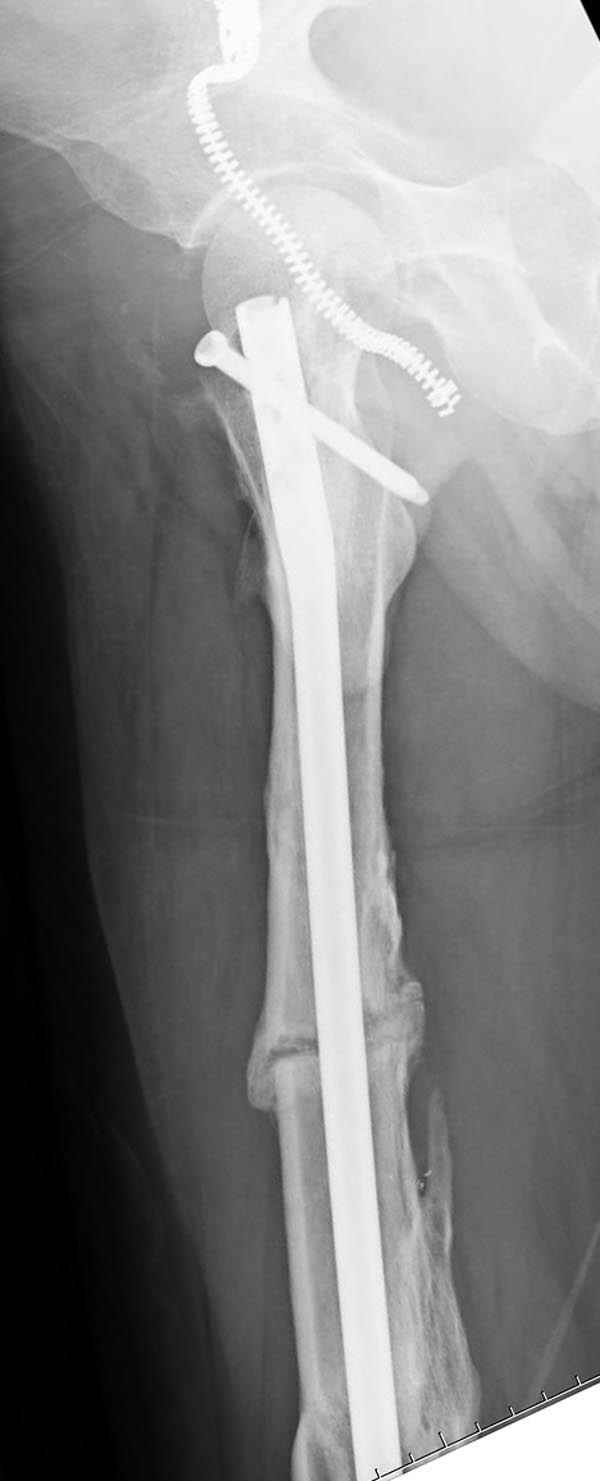

Мы не дождались “Happy End”, у больного IQ в пределах 70%, через 6 месяцев вернулся после небольшой травмы, споткнувшись получил перелом

того же бедра (рис №7).

На следующий день произвели интрамедуллярный остеосинтез: этапы во время операции (рис №8, №9)

и последующих снимках (рис №10, 11, 12, 13) перелом сростается и передвигается с полной нагрузкой.

При обзоре причин перелома, на снимке №2 обнаружили, что один из стержней аппарата наружной фиксации проходил только через передний кортекальный слой, что создало стрессовую зону на бедре и в результате перелом из-за незначительной травмы.